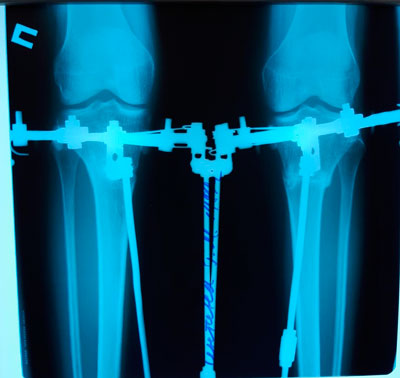

Пациентка - 30 лет.

Дата операции - 04.04.2019г.

Дата снятия аппаратов - 02.07.2019г.

Срок сращения - 89 дней.